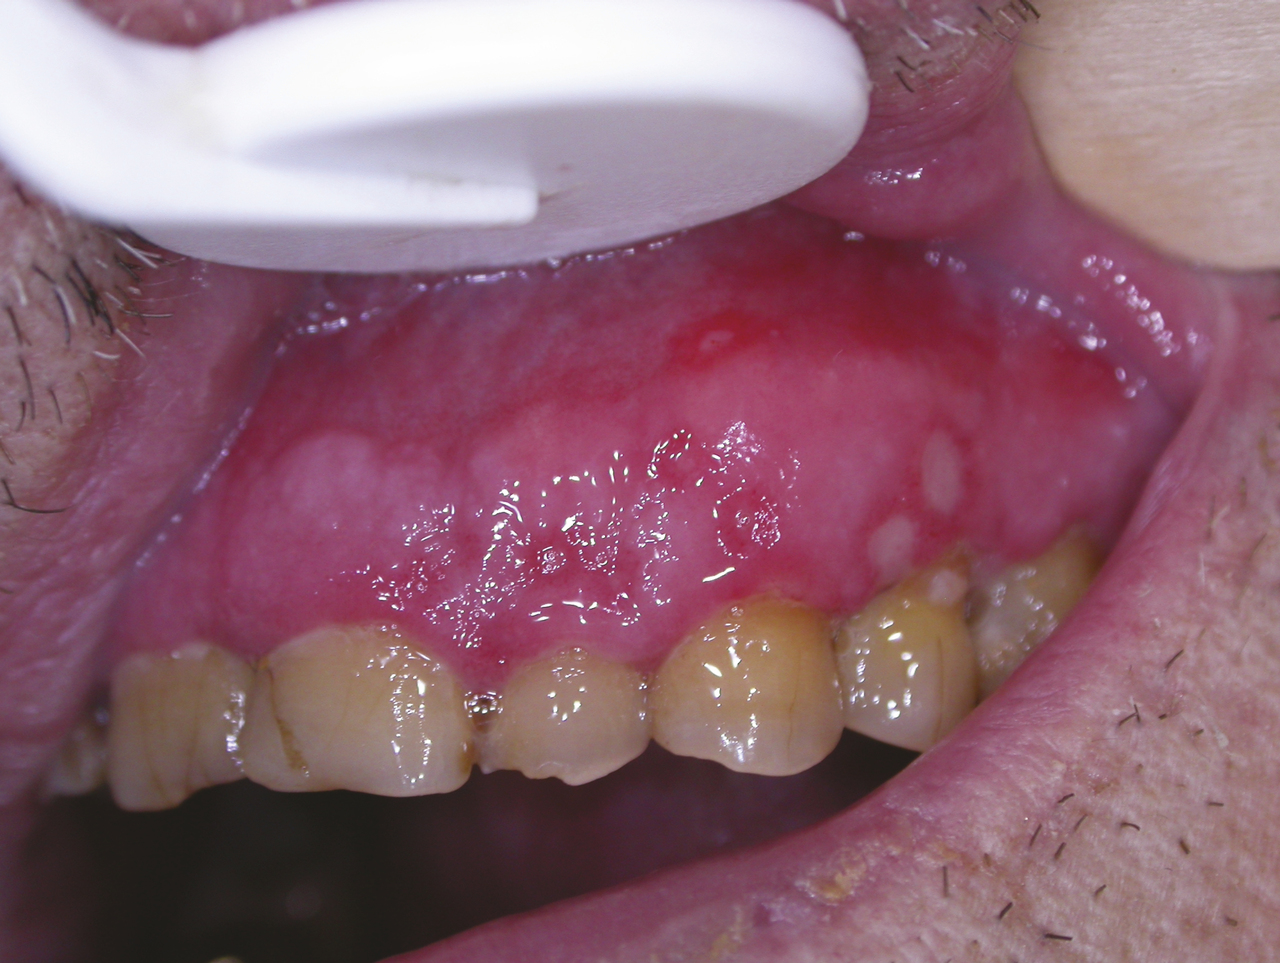

Les stomatites mycosiques sont le plus souvent dues à Candida albicans, levure saprophyte du tube digestif, de la peau et des muqueuses ; l’infection est opportuniste à la faveur d’une modification du terrain entraînant un déficit immunitaire local : diabète, endocrinopathie, hémopathie maligne, infection par le VIH, déficit immunitaire transitoire ou permanent ; traitement médical (antibiothérapie, corticothérapie systémique ou locale avec les traitements inhalés) ; affection locale (sécheresse buccale, carcinome buccopharyngé, mauvais état dentaire, prothèses dentaires, tabagisme). La mycose aiguë se traduit par une efflorescence d’enduits ou de pseudo-membranes blanchâtres (joues, palais) appelée « muguet », détachables par grattage d’une muqueuse érythémateuse (fig. 9). Les signes fonctionnels sont peu intenses : sécheresse buccale, sensation de cuisson, goût métallique. La glossite losangique médiane traduit une infection chronique par Candida albicans. La lésion siège sur la partie médiane de la face dorsale de la langue, en avant du V lingual ; elle a une surface lisse, rosée ou rouge, plane ou mamelonnée, de forme grossièrement losangique à grand axe antéro- postérieur (fig. 10) avec peu de signes fonctionnels ; une lésion érythémateuse en miroir siège sur le palais. Un prélèvement pour culture mycologique est utile. Le traitement repose sur les antifongiques locaux, amphotéricine B, nystatine en suspensions buvables, miconazole en gel buccal. En cas d’inefficacité ou chez les patients immunodéprimés, un traitement systémique est instauré (fluconazole).